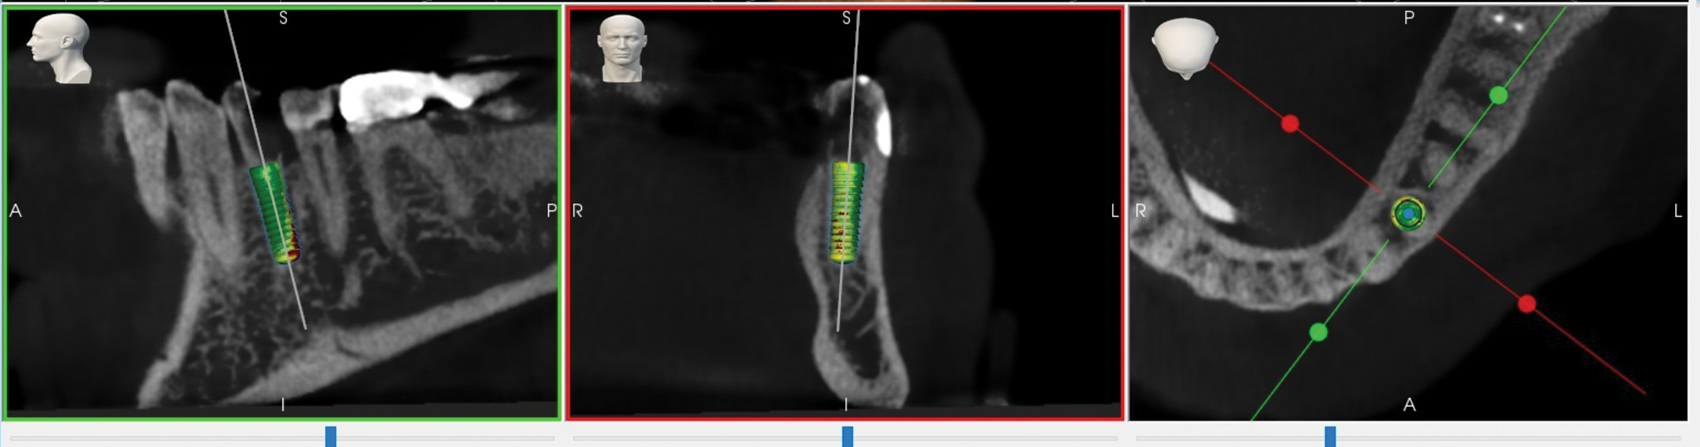

The surgical intervention was planned on the same day as the surgery using digital imaging and communication in medicine (DICOM) files from a CBCT scan of the patient. An intraoral splint was mechanically retained on the patient's stable dentition using hard-locking dental material and monitored for proper fixation. A fiducial array was affixed to the intraoral splint during CBCT scanning to allow for eventual registration of the patient location (Figure 1). Using 3D graphics and 2D cross-sections in the RADS planning software (Yomi®-Enabled Surgery, Neocis, Inc., neocis.com), the surgeon virtually optimized the depth and future insertion axis of the 4.1-mm x 10-mm dental implant (SLA® Bone Level, Straumann, straumann.com). The existing tooth was used as a relative guide for restorative-driven planning (Figure 2).

A mathematical algorithm was implemented to analyze the deviation between the planned (Figure 2) and actual implant placement (Figure 8). Implant placement versus the plan was evaluated using an automated superimposition of the preoperative plan and the postoperative CBCT plan. In line with methodologies advised in the International Team for Implantology (ITI) consensus reports,5 the algorithm assessed deviation between the planned and actual implant placement in terms of coronal and apical depth, lateral, and global deviations, as well as angular deviation. Results from this RADS case (Table 1) were comparable to those calculated in the ITI consensus meta-analysis of surgical guide accuracy, which reported mean global coronal deviations of 0.9 mm (CI: 95% [0.8-1 mm]), global apical deviations of 1.2 mm (CI: 95% [1.1-1.2 mm]), and angular deviations of 3.3 degrees (CI: 95% [2.1-4.6 degrees]).5

Fig 2. Virtual placement of the implant in RADS planning software.

Figure 2

Fig 8. Comparison between the actual implant placement (shown here) and the planned position (Fig 2) was analyzed.

Figure 8